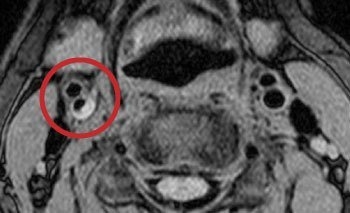

脳血管画像(MRA)

頸動脈の血栓(プラーク)

脳ドック

脳血管疾患の多くは何の前触れも無く起こり、発症してからの治療では重い後遺症が残ることも少なくありません。脳ドックでは、脳と脳・頚部血管の病気の早期発見と予防を目指して各種検査を行います。

脳ドックでわかること

まだ症状の出ていない脳の病気や脳血管の病気を発見することができます。

1. 脳梗塞

2. 未破裂脳動脈瘤

3. 無症候性脳梗塞

4. 脳・頚部血管の閉塞・狭窄

5. 脳卒中の危険因子

検査内容

• 問診・診察・身体測定・血圧測定

• 血液検査(GOT、GPT、γ-GTP、中性脂肪、HDLコレステロール、LDLコレステロール、空腹時血糖、HbA1c)

• 尿検査(糖、蛋白)

• 心電図

• MRI(磁気共鳴断層撮影)

• MRA(磁気共鳴脳血管撮影、頸部含む)